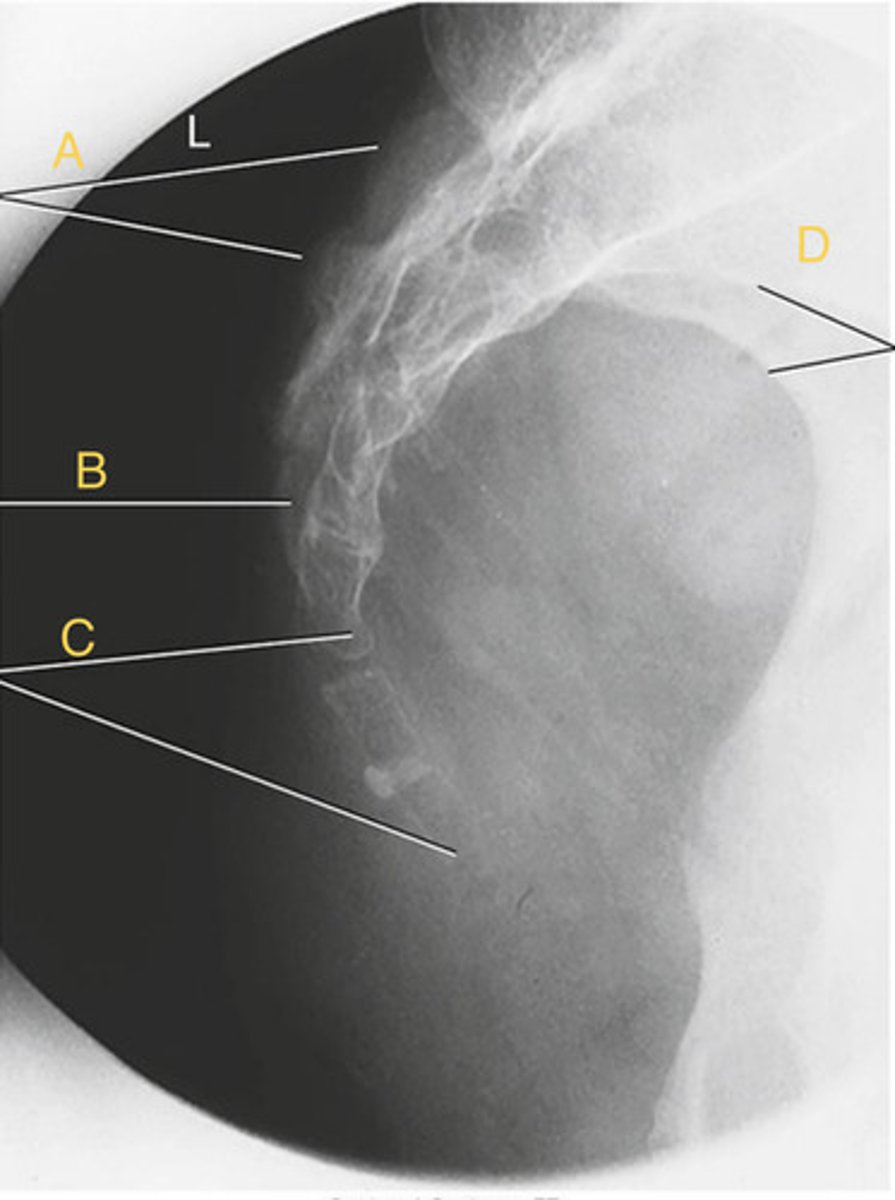

L2 Transverse process

A.

L3 Pedicle

B.

L3 pars interarticularis

C.

L3 inferior articular process

D.

L4 Superior articular process

E.

L3-4 zygapophyseal joint

F.

Oblique lumbar

What position?